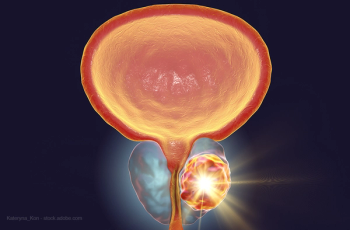

Researchers identify 18F-PMSA-1007 as an equally effective radiopharmaceutical for detecting prostate cancer.

Molecular imaging technique performs better with detection, staging, and determining treatment plans.

Thirty-two men participated in the retrospective study.

PSA-density does not appear to significantly improve its diagnostic performance.

A structured template for PI-RADS may increase the diagnostic performance of prostate MRI for clinically significant prostate cancer.

MR imaging of the prostate detects more treatable cancers and reduces overdiagnosis than standard ultrasound-guided biopsies.

Compared to standard biopsy strategy, MR imaging-guided strategies are cost effective in helping detect prostate cancer.